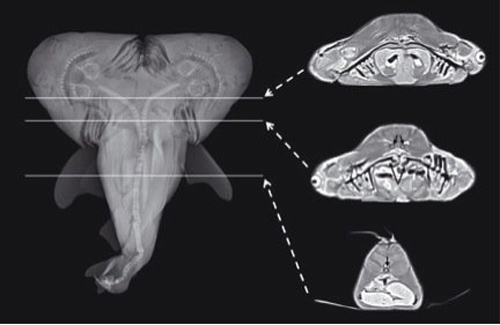

5. Bào thai cá mập 2 đầu

Vào tháng 3 năm nay, các nhà nghiên cứu đã báo cáo một trường hợp kỳ lạ về một con cá mập bò mang thai được đánh bắt ngoài khơi Florida Keys. Con cá mập này mang bào thai không chỉ có một mà những hai cái đầu. Biến dạng này xảy ra khi phôi thai cá mập cố gắng chia thành cặp song sinh đầu trong quá trình phát triển nhưng không thành công. Các nhà nghiên cứu cũng cho biết, nếu được sinh ra con cá mập này sẽ không thể sóng sót lâu trong tự nhiên.